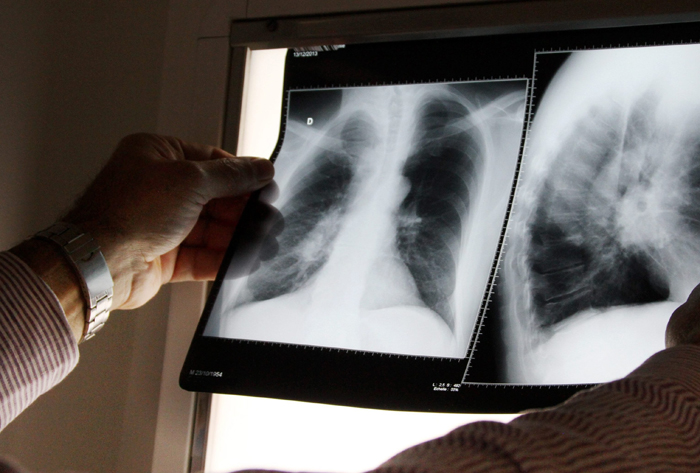

Le patient tousse (il peut y avoir un peu de sang dans les crachats). Il a de la fièvre, des sueurs nocturnes, il n'a plus d'appétit, maigrit, peut ressentir des douleurs à la poitrine. Il est très fatigué. Tous ces symptômes concernent la tuberculose pulmonaire.

La tuberculose peut avoir des conséquences graves si elle n'est pas prise en charge comme une compression des voies respiratoires, un épanchement de liquide dans la plèvre….

Le traitement consiste à détruire les bactéries avec une association de quatre antibiotiques. Les patients doivent être isolés. Un vaccin existe.